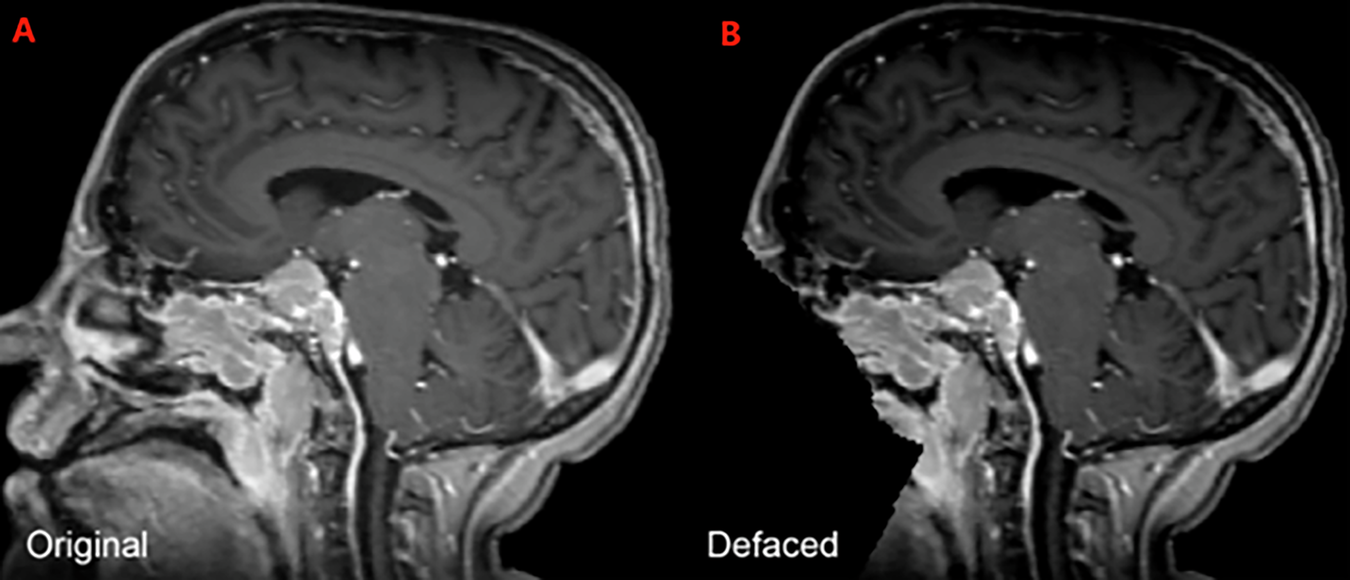

Example of a sagittal image of a brain MRI from the BraTS-MEN-RT training set, both before (A) and after (B) automated defacing.